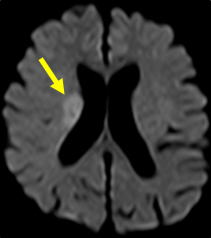

脳梗塞は発症してもすぐにCTやMRIで所見が出るわけではありません。最も感度の良い「拡散強調画像」という特殊な検査法でも、発症から約30分から1時間ほど経たないと異常は発見できません。従って、ごく早期の脳梗塞は「脳卒中の症状があり、CTで出血がなければ脳梗塞」と診断するわけです。また、CTでは診断に限界がある場合も多く、MRI検査が必要です。当院では症状のある患者さんは最優先にMRI検査(24時間稼働)をしております。(図1)

図1:脳梗塞のMRI拡散強調画像。矢印の部位が淡く白くなっています。 |